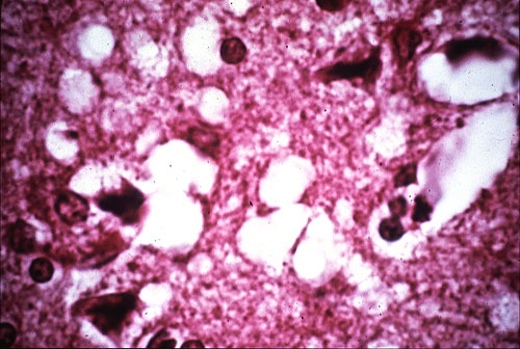

Tessuto colpito dalla BSE

La particolarità della forma anomala di questa proteina, o PrPsc (Prion Protein Scrapie), è quella di convertire nella forma anomalla le altre proteine PrPc con cui entra in contatto. Le PrPsc si accumulano quindi nei neuroni, danneggiandoli e provocando lesioni encefaliche, che appaiono all’esame microscopico come aree otticamente vuote e che ricordano appunto l’aspetto di una spugna.